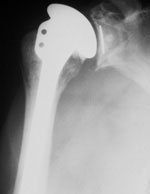

L’ARTHROPLASTIE TOTALE OU PARTIELLE DE L’ÉPAULE.

La prothèse d’épaule est devenue une intervention de routine dont les trois indications types sont les suivantes, l’arthrose, certaines fractures, la rupture massive non réparable de la coiffe des rotateurs.

LE TRAITEMENT CHIRURGICAL PAR PROTHESE D'EPAULE

L'intervention consiste à remplacer les surfaces articulaires usées par des pièces prothétiques.

Deux solutions s’offrent alors à nous:

Soit la coiffe très abimée ou absente

au quel cas on mettra en place une prothèse inversée. Qui permet par sa forme de suppléer aux tendons absents.

soit la coiffe est conservée et de bonne qualité,

ce qui est rare dans le contexte avec des patients souvent multi-infiltrés, alors on met en place une prothèse standard totale ou partielle